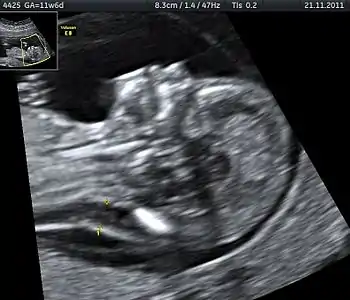

A nuchal scan or nuchal translucency (NT) scan/procedure is a sonographic prenatal screening scan (ultrasound) to detect chromosomal abnormalities in a fetus, though altered extracellular matrix composition and limited lymphatic drainage can also be detected.[1]

There are two distinct measurements: the size of the nuchal translucency and the thickness of the nuchal fold. Nuchal translucency size is typically assessed at the end of the first trimester, between 11 weeks 3 days and 13 weeks 6 days of pregnancy.[3] Nuchal fold thickness is measured towards the end of the second trimester. As nuchal translucency size increases, the chances of a chromosomal abnormality and mortality increase; 65% of the largest translucencies (>6.5mm) are due to chromosomal abnormality, while fatality is 19% at this size.[2] A nuchal scan may also help confirm both the accuracy of the pregnancy dates and the fetal viability.

Procedure

Nuchal scan (NT procedure) is performed between 11 and 14 weeks of gestation, because the accuracy is best in this period. The scan is obtained with the fetus in sagittal section and a neutral position of the fetal head (neither hyperflexed nor extended, either of which can influence the nuchal translucency thickness). The fetal image is enlarged to fill 75% of the screen, and the maximum thickness is measured, from leading edge to leading edge. It is important to distinguish the nuchal lucency from the underlying amniotic membrane.[8]

Normal thickness depends on the crown-rump length (CRL) of the fetus. Among those fetuses whose nuchal translucency exceeds the normal values, there is a relatively high risk of significant abnormality.